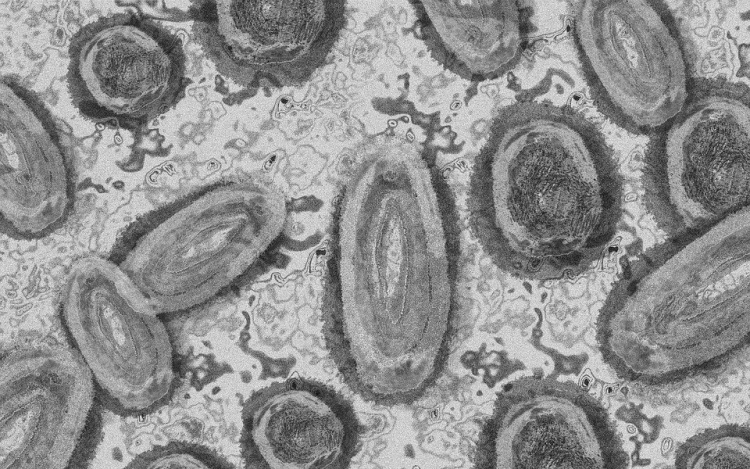

Megfertőződött majomhimlővel egy négyéves kislány Németországban - jelentették kedden német hírportálok az országos közegészségügyi intézet (RKI) adatai alapján.

Németországban első alkalommal mutatták ki a kórokozót gyermek szervezetében.

A kislány két fertőzött felnőttel él együtt a Baden-Württemberg tartományi Pforzheimben. A tartományi egészségügyi minisztérium tájékoztatása szerint elővigyázatosságból vizsgálták meg, miután kimutatták az első fertőzést a háztartásban. Eddig nem jelentkeztek nála a betegség tünetei.

Az RKI-nál május elején regisztrálták az első németországi majomhimlős eseteket. Keddig 2982 igazolt fertőződést jegyeztek fel. A betegség mind a 16 tartományban megjelent.

Az intézet ismeretei szerint a vírus elsősorban szexuális úton terjed Németországban, főleg férfiak körében. A fertőzöttek szinte mind felnőtt férfiak, csupán hét nő és két kiskorú - egy 15 és egy 17 éves kamasz - van közöttük.

Az esetek többségében a fertőzés enyhe lefolyású betegséggel jár. Halálos áldozatot Németországban még nem regisztráltak.

Az Afrika egyes részein évtizedek óta ismert és ritkán előforduló majomhimlő május óta Európában, Észak-Afrikában és más térségekben is terjed. Az Egészségügyi Világszervezet (WHO) júliusban globális egészségügyi vészhelyzetnek nyilvánította a járványt.